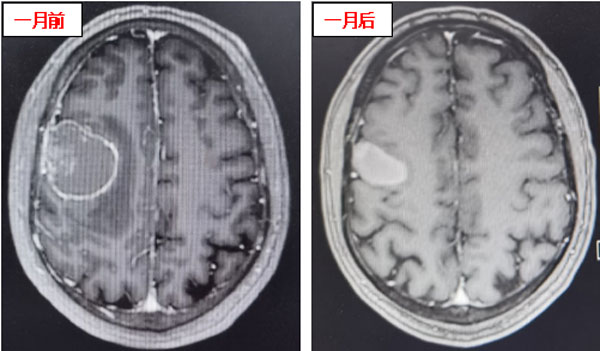

患者在接受3次射波刀治疗后,头痛症状明显减轻,癫痫症状消失,肢体肌力明显好转。接受治疗1个月后,患者肢体肌力恢复正常,未再出现口角、肢体抽搐及头痛、头晕等症状,仅左侧手指尖偶有麻木感。复查头颅核磁显示:颅内病灶明显缩小,周围无明显水肿坏死征象,安全性良好,这意味着射波刀治疗成功遏制了颅内转移瘤。